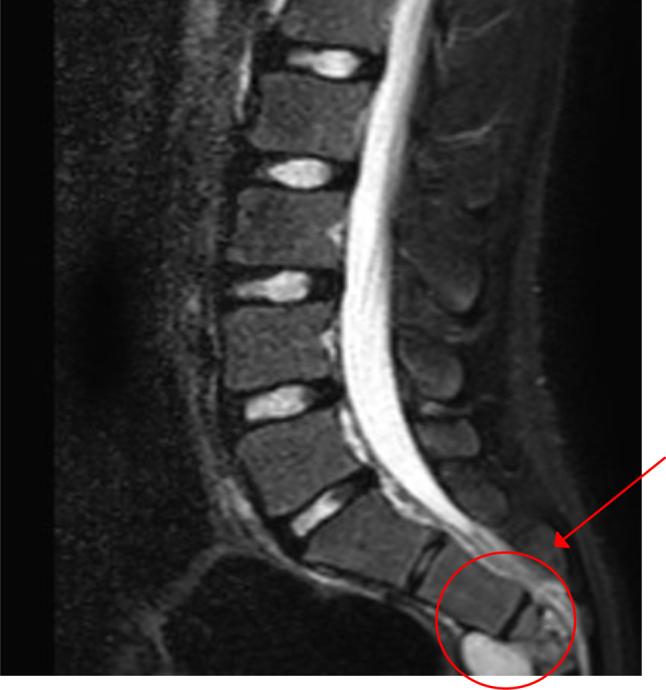

A 17-year-old male with a history of HC disease presented with low back pain radiating to both lower limbs, claudication, and chronic constipation for 5 years. Imaging revealed a large, multiloculated sacral cyst extending retrorectally and presacrally from S3 to S5, involving the spinal canal, compressing the rectum, and causing sacral erosion. A diagnosis of sacral hydatidosis was made, and the patient was started on albendazole, with surgical excision planned.

一名有HC病病史的17岁男性,出现下背部疼痛并放射至双下肢、间歇性跛行及慢性便秘达5年。影像学检查显示一个巨大的、多房性骶骨囊肿,从S3至S5向直肠后方和骶骨前方延伸,累及椎管,压迫直肠,并导致骶骨侵蚀。诊断为骶骨包虫病,患者开始服用阿苯达唑,并计划进行手术切除。